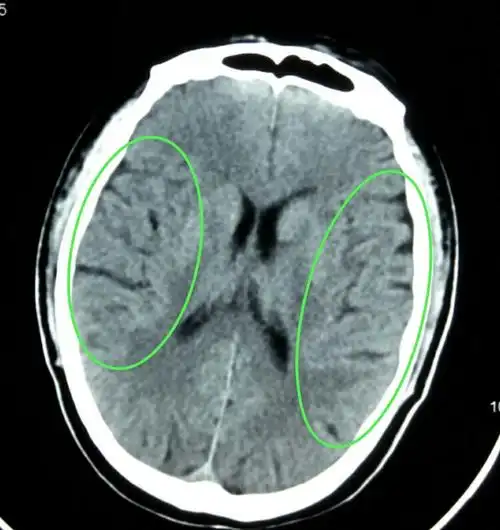

头痛,头晕,耳呜,失眠.做脑ct是脑萎缩

体检发现头颅ct局限脑萎缩

头颅ct平扫显示脑皮层萎缩.

患者虽然已80岁,脑萎缩及脑梗死并不严重.

病人女,37岁,间断性头痛史,其他无特殊,既往健康,脑萎缩较明显,需要不